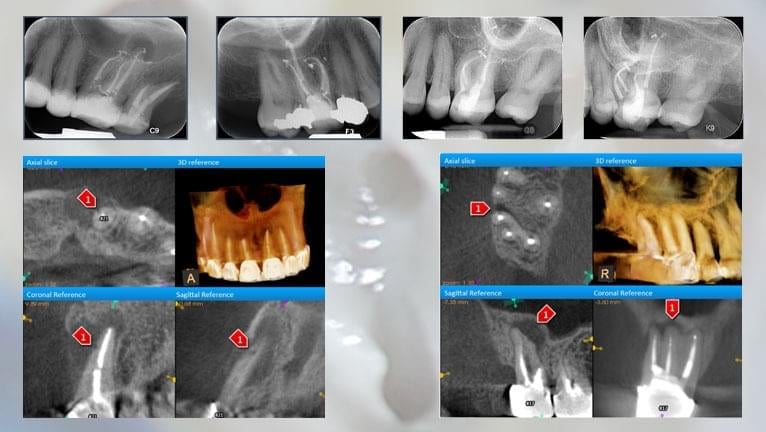

THE USE OF CBCT TECHNOLOGY IN ENDODONTICS

Join Dr. Nahmias and Dr. Stephen Phelan for a free webinar teaching the GP how to the use of CBCT Technology for diagnosis and treatment of complex endodontic cases. Dr. Nahmias will show a series of cases and explain the decision making process and rationale for the use of 3D Imaging.

This webinar will feature a number of interesting and informative cases from Dr. Nahmias’s specialty practice.